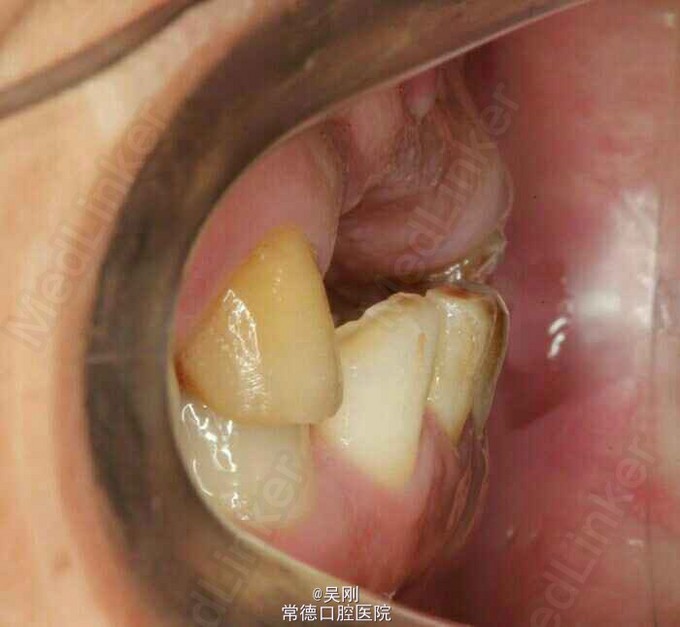

11、12、21缺失,牙槽骨(唇侧更明显)吸收严重成月牙状。 22残根断面距龈上约1.5mm,13牙髓坏死。 深覆 牙合 。 下前牙之间有间隙。 缺牙区距离太长,超过实际距离。 X线显示下前牙与上颌缺牙区牙槽嵴角度成反 牙合 。